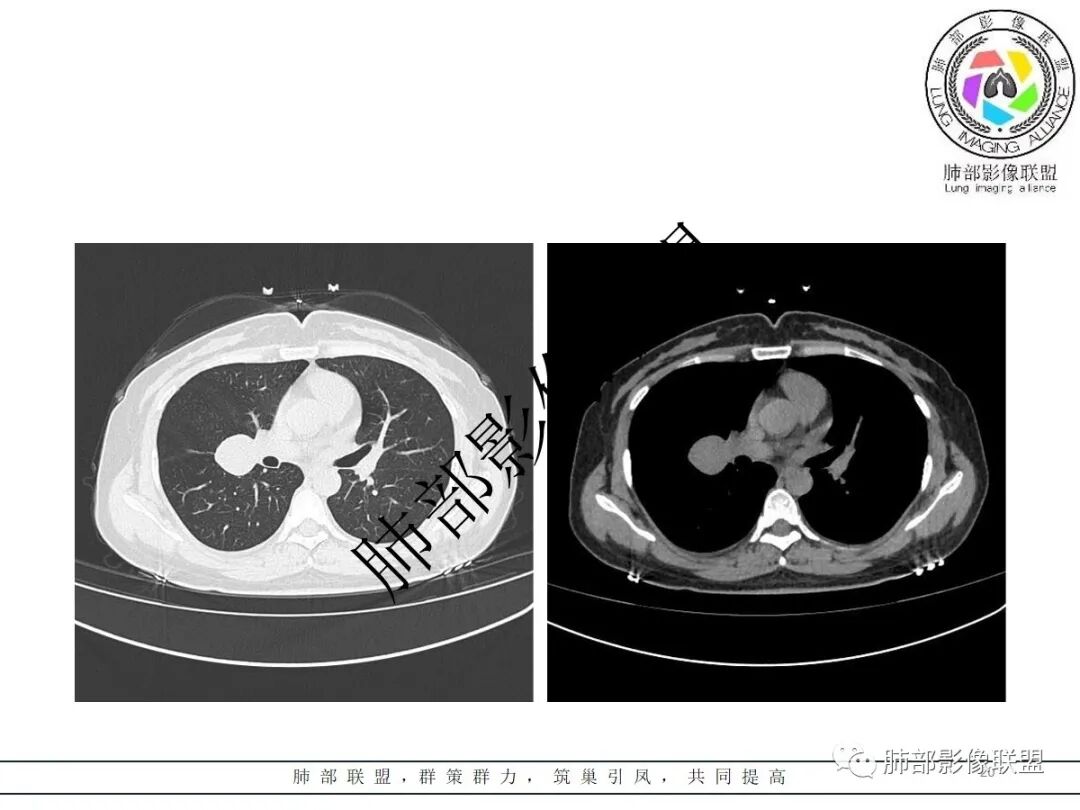

右肺门类圆形实性肿块,边缘光滑,无分叶毛刺,跨叶,推移血管,密度均匀,增强延迟强化相对明显,未见坏死及血管造影征。

2.右肺水平叶裂斜叶裂肺门交界区类椭圆形块影,表面光整,未见分叶毛刺及棘状突起,未见邻近结构牵拉。与邻近支气管无关联。

3.病灶密度均匀,未见液化坏死、钙化及脂肪低密度。轻度强化,可见纤细血管影蜿蜒穿行。右肺动脉推移变形,未见侵入或充盈缺损。

4.灶周未见磨玻璃晕或极低密度影环绕。右肺下叶背段胸膜下见微小实性密度结节影,边界清楚。

4)发生于肺表面(近脏层胸膜或叶间裂),强化不显著,可见穿行血管,与本例的符合程度是最高的。